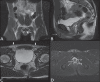

Magnetic resonance imaging is a method with high contrast resolution widely used in the assessment of pelvic gynecological diseases. However, the potential of such method to diagnose vaginal lesions is still underestimated, probably due to the scarce literature approaching the theme, the poor familiarity of radiologists with vaginal diseases, some of them relatively rare, and to the many peculiarities involved in the assessment of the vagina. Thus, the authors illustrate the role of magnetic resonance imaging in the evaluation of vaginal diseases and the main relevant findings to be considered in the clinical decision making process.